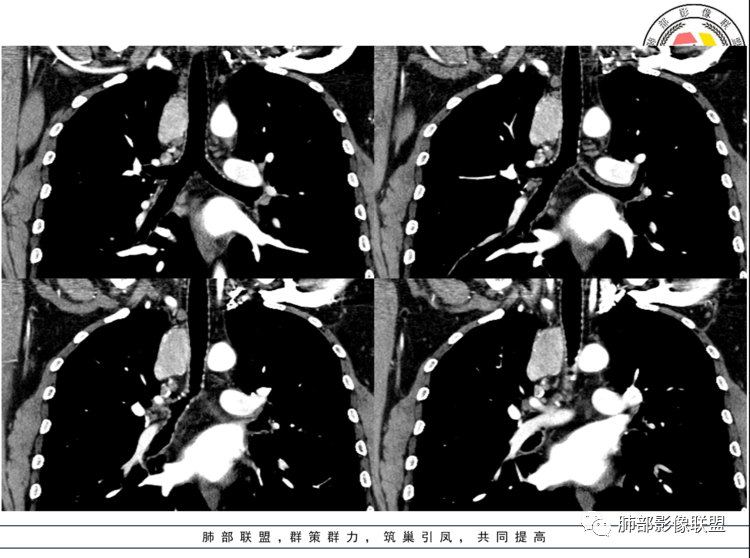

男,40岁,体检发现纵隔占位

•查血常规、血生化、肿瘤标志物、尿常规大致正常。气管腔静脉间隙团块状影,密度均匀,边界清楚,增强扫描,明显的强化,肿块的周围气管旁见多个肿大的淋巴结,强化特点类似。考虑良性占位,巨淋巴增生症。需要与异位胸腺瘤、结节病、淋巴瘤、副神经节瘤、淋巴结转移瘤鉴别。

患者中年男性,体检发现纵隔占位。胸部CT:右上前纵隔不规则占位灶,位于上腔静脉后方,血管无推移,边缘光滑,密度均匀,增强动脉期明显强化,综合考虑良性病变,巨大淋巴结增生症可能大。鉴别神经源性肿瘤。

定位,中纵隔,上腔静脉向前推移。椭圆形软组织影,边界清晰,密度均匀,周围脂肪间隙清晰。增强明显均匀强化。

考虑,良性,CD,鉴别副节瘤。

动脉期显著强化,结节呈“门状结构”附近多发子灶——CD!

3.1单发型CD的肺部表现

单发型CD多为透明血管型,所以明显强化和中央分枝状钙化具有特征性。在CT上表现圆形或类圆形软组织密度影,伴或不伴周围淋巴结增生,体积一般较大,边缘光整,病灶中央的弧形、线样、分枝样及枯枝样钙化(因为肿块内增生的血管组织玻璃样变或退变后钙盐沉积,故多呈血管样铸型的分支状或枯枝状);透明血管型因为其内血供丰富,周围可见粗大的供血动脉,在多期扫描动脉早期明显强化,强化程度与大血管相仿,又由于病灶内血管壁玻璃样变或纤维化及内皮细胞过度增生致血管腔狭窄,对比剂退出减慢,故延迟扫描扫描仍可持续强化,呈“早进晚出”的强化方式。因为其血供丰富,坏死、囊变或出血少见,但是有时候病灶内灶状或条片状低密度影,是纤维组织或发生玻璃样变性的血管结构,而不是缺血坏死区。